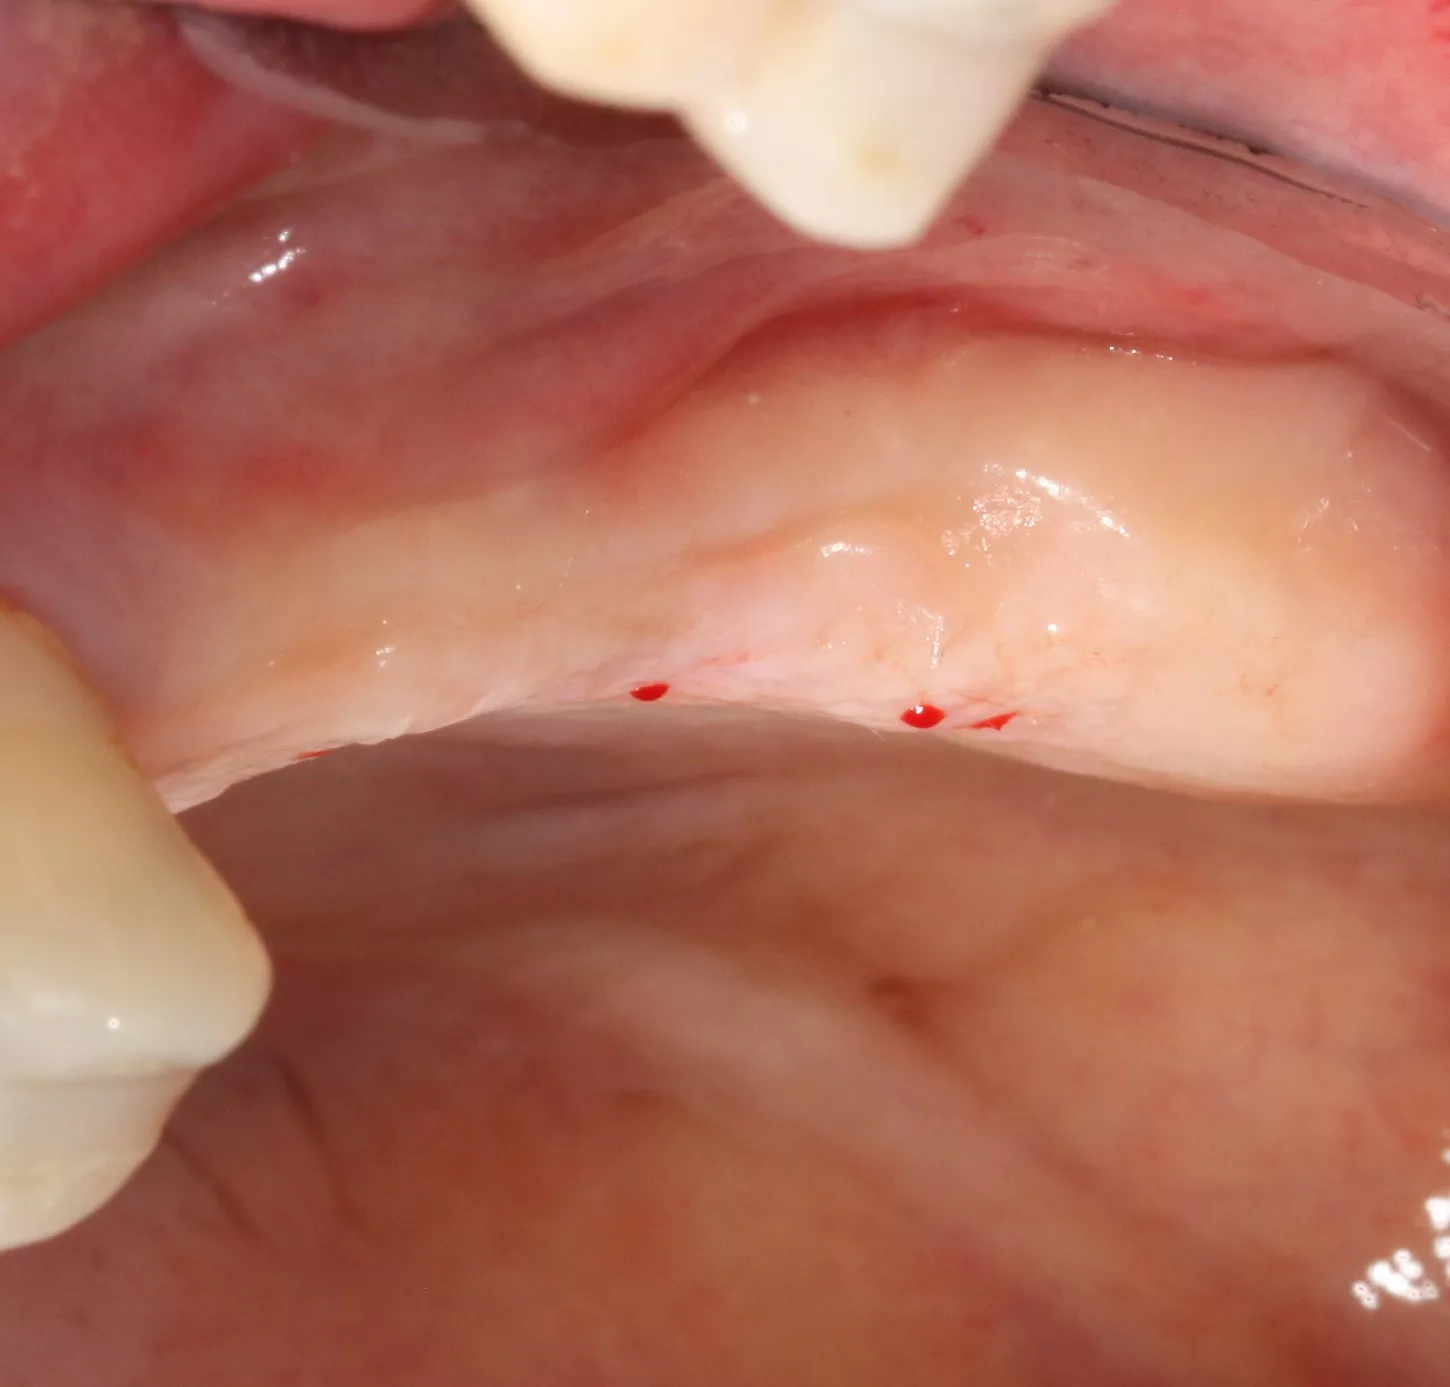

5. A full-thickness flap was elevated and a releasing incision made mesial to 24. Care must be taken at this stage not to damage the periosteum.